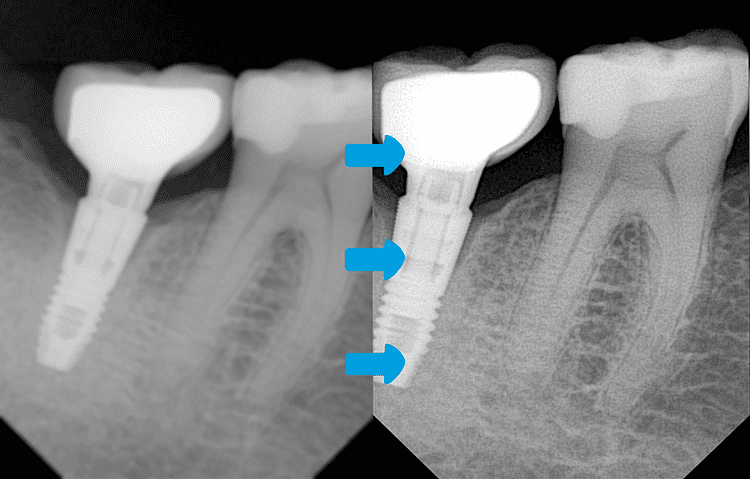

Scharfzeichnungsalgorithmus für die apikale Radiographie

Revolutionäre Präzision für einwandfreie zahnmedizinische Diagnosen

Entdecken Sie einen bedeutenden Durchbruch in der Dentalbildgebung

Unser intelligenter Scharfzeichnungsalgorithmus – speziell für die apikale Radiographie entwickelt – liefert beispiellose diagnostische Klarheit durch hochleistungsfähige Bildverarbeitung.

- Verbesserte Klarheit & Präzision für präzise Diagnostik

- Reduzierte Unschärfe & Artefakte – selbst bei komplexer Anatomie

- Das Unsichtbare sichtbar machen – Präzisionsdiagnostik neu definiert

- Nahtlose Integration – Keine zusätzliche Hardware erforderlich